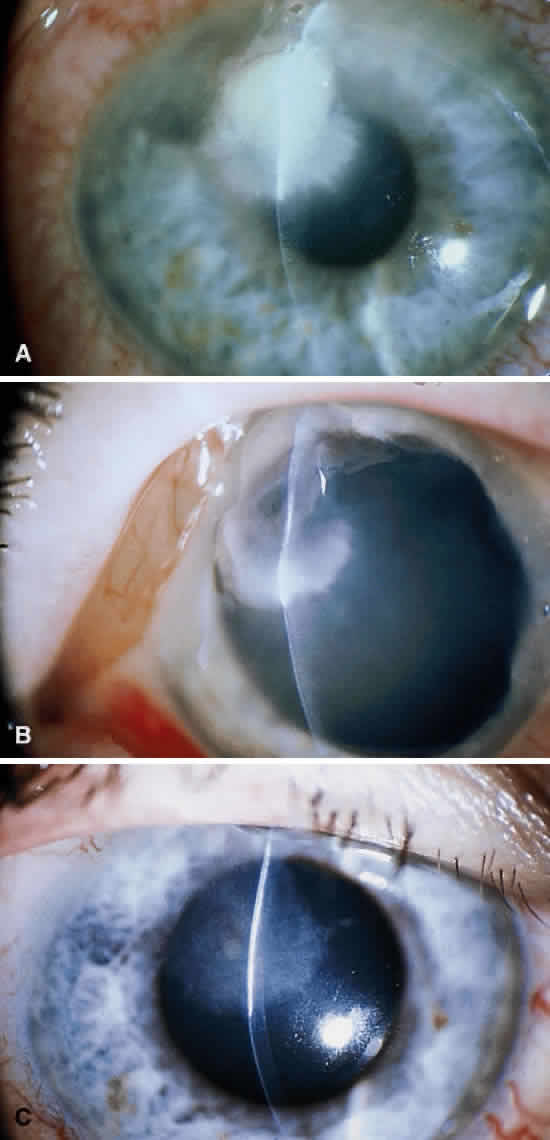

Clinically, the infected staphylococcal corneal ulcer presents with a yellow-white, well-demarcated area of infiltrate, which appears directly beneath an epithelial defect (Fig. 2). On occasion, multiple, small satellite lesions may develop. The infection may initially be superficial; however, if inadequately treated it can produce a mid to deep stromal abscess that may eventually lead to perforation. Stromal edema and white blood cell migration frequently surround the dense infiltrate and clear as the infection comes under control. Although there may be a marked anterior chamber reaction with hypopyon, the ulcer more frequently is indolent, with only a minimal inflammatory reaction.34

The more peripheral marginal infiltrate is sterile and is caused by a hypersensitivity reaction to the exotoxin or the bacterial antigens of S. aureus.35,36 The peripheral infiltrates usually are associated with blepharitis or conjunctivitis and frequently begin in the areas where the lid margins cross the limbus (at 2-, 4-, 8-, and 10-o'clock positions). The lesions often have a typical clinical appearance characterized by one or more small, well-circumscribed anterior stromal infiltrates, with a lucid interval between them and the limbus (Fig. 3). Although the epithelium is usually intact, it may break down, leading to ulceration, scarring, and neovascularization.